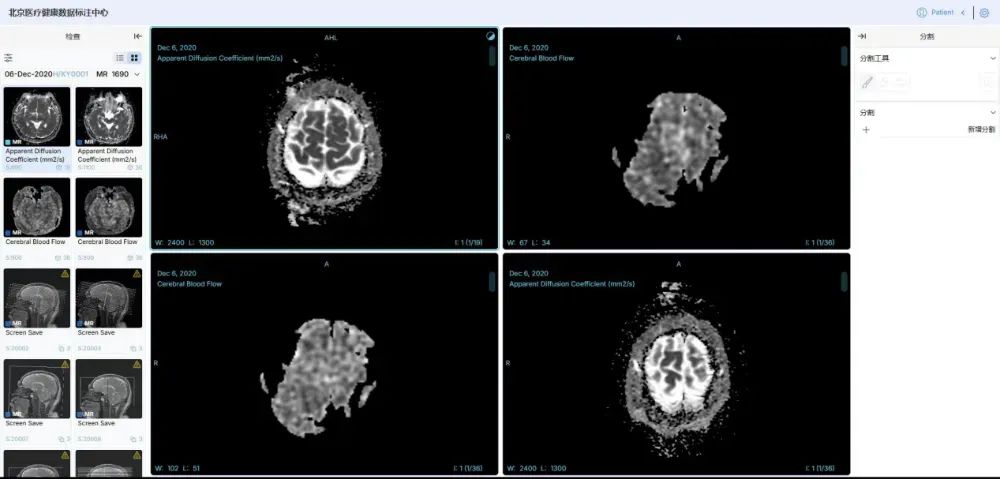

规模大、维度全、安全可信的高质量数据集。中国联通联合国内多家顶尖医疗机构,构建了覆盖影像、诊疗、药品等全维度的高质量数据集,其中,数据集总规模达 100TB,胸部CT影像数据集标注2万余例,肺结核辅助诊断模型准确率超95%;耳部CT影像数据集标注5000余例,听觉障碍识别准确率达95%;肾脏病慢病管理数据集整合1万例患者全周期数据,风险预警模型准确率突破95%;药品说明书数据集涵盖58000份药品信息,实现用药风险智能解析与动态评估。

在数据治理与管理方面,中国联通构建医疗健康行业可信空间,制定数据脱敏规范,运用数据沙箱和隐私计算双引擎处理数据,确保“原始数据不出域、数据可用不可见”。建立11项数据治理全流程运营标准,通过多维度举措保障数据质量与安全。例如,在胸部CT影像数据标注中,采用双盲标注和专家抽样审核,确保标注一致性评估结果超95%,准确性达98%以上。

高效、准确的系列医疗专科智能体。基于该高质量数据集,中国联通研发了一系列医疗专科智能体。基于胸部CT影像的肺结核疾病筛查与诊断模型智能体,准确率超 95%,可实现分钟级快速检测;肾脏病慢病管理干预模型智能体、耳部疾病辅助诊断模型智能体,助力医务人员提高诊断效率及诊疗方案准确性;药品全生命周期智能评估模型智能体,为药品研发、监管等提供全链条数据支撑。